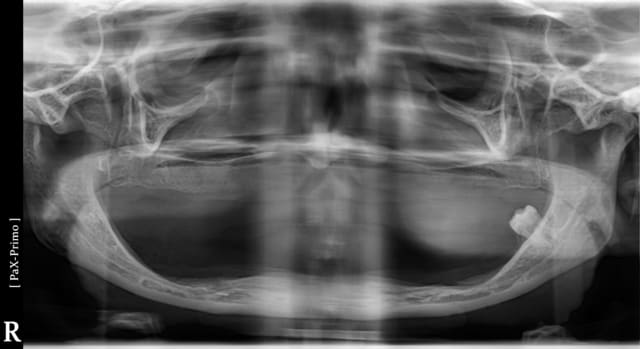

cette patiente vient me voir pour poser des implants, elle est edentée complet maxillaire et mandibulaire, et se plaint de l'instabilité de ses deux complets, elle voulait se faire faire ca au portugal mais j ai soigné une amies à elle tres contente du resultat, qui lui conseil de venir me voir, donc avant de partir elle voudrait mon avis.

Et la c'est la surprise, la panoramique parle d'elle meme.

Ah oui j 'ai oublié de dire que la patiente à 38 ans...